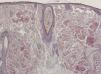

HistopatologíaEl estudio histológico de la lesión mostró atrofia epidérmica y el depósito de un material amorfo y eosinófilo, ocupando de forma difusa la dermis papilar y reticular. Junto al depósito se observaba un escaso infiltrado de células plasmáticas (fig. 2). La tinción Rojo Congo evidenció intensa birrefringencia verde-manzana con luz polarizada (fig. 3 A). Con la tinción de tioflavina el material depositado presentaba fluorescencia con el microscopio de epiluminiscencia (fig. 3 B).

La histopatología muestra una epidermis atrófica y el depósito de un material amorfo y eosinófilo ocupando la dermis y la hipodermis. También es característica la presencia de un infiltrado plasmocitario perivascular.